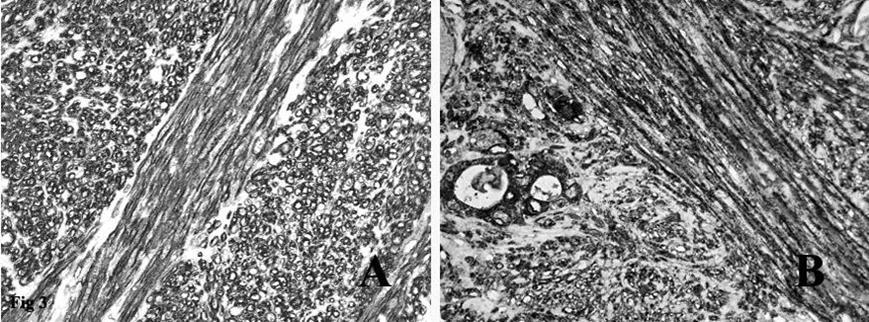

Figure 3.A. Immunohistochemical stain on the fascicles of tumor cells intersecting each other at right angles was strongly positive for smooth muscle actin. B. Immunohistochemical stain on the spindle tumor cells and on the residual thyroid follicles was positive for EMA.

Immunohistochemistry showed that the tumor spindle cells were strongly immunoreactive for vimentin, that is expressed by mesenchymal cells, actin HHF35, actin 1A4 (Figure 3A) and desmin, that are useful markers for the identification of smooth muscle cells. Finally, the spindle cells were positive for EMA (Figure 3B), a representative marker of epithelial cells.